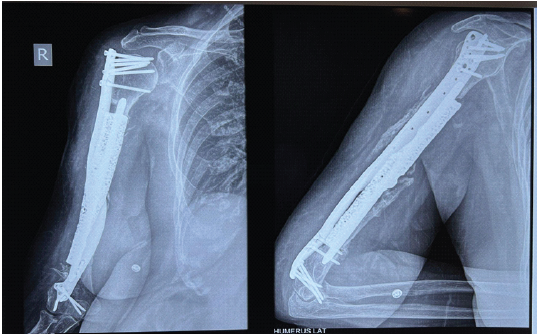

The printed prosthesis was designed to retain and integrate the existing viable spikes of bone in the proximal and distal segments while recreating the lost mid-segment. This feature ensured that the implant would integrate with the patient’s existing bone structure, promoting long-term stability and functionality. To provide additional stability, a long, customized titanium plate was designed and printed. This plate played a crucial role in holding the distal fragment in place, allowing for proper bone healing and alignment. Six locking screws were employed on the humerus head to maximize bone purchase and ensure secure fixation. Locking screw fixation given on the distal humerus was performed from lateral to medial on the condyles. Post-operative radiographs obtained at the 3-month follow-up showed the 3D-printed humeral prosthesis and plate in situ with maintained alignment and no evidence of implant loosening or failure (Fig.3).

Figure 3: Post-operative radiograph showing prosthesis and plate.